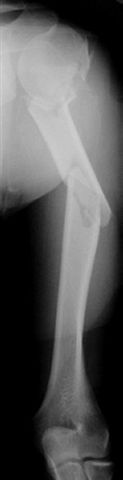

Well, to date he is still on abduction splint with traction applied to a wire placed through the olecranon. Images attached. The acetabulum

was ORIFed. The humerus is still discussing...

The views you now show demonstrate an extra articular fracture with good alignment on the AP, and some displacement on the lateral.

This should be able to be managed with adjustment of the traction.

Ilizarov is probably the best fixation if you decide to do so. However, it will heal with nonoperative treatment, with painless, reasonable

function. Even if it does not heal primarily, the pieces will heal enough to become a single level problem, readily solved with compression

plating. Jim Carr